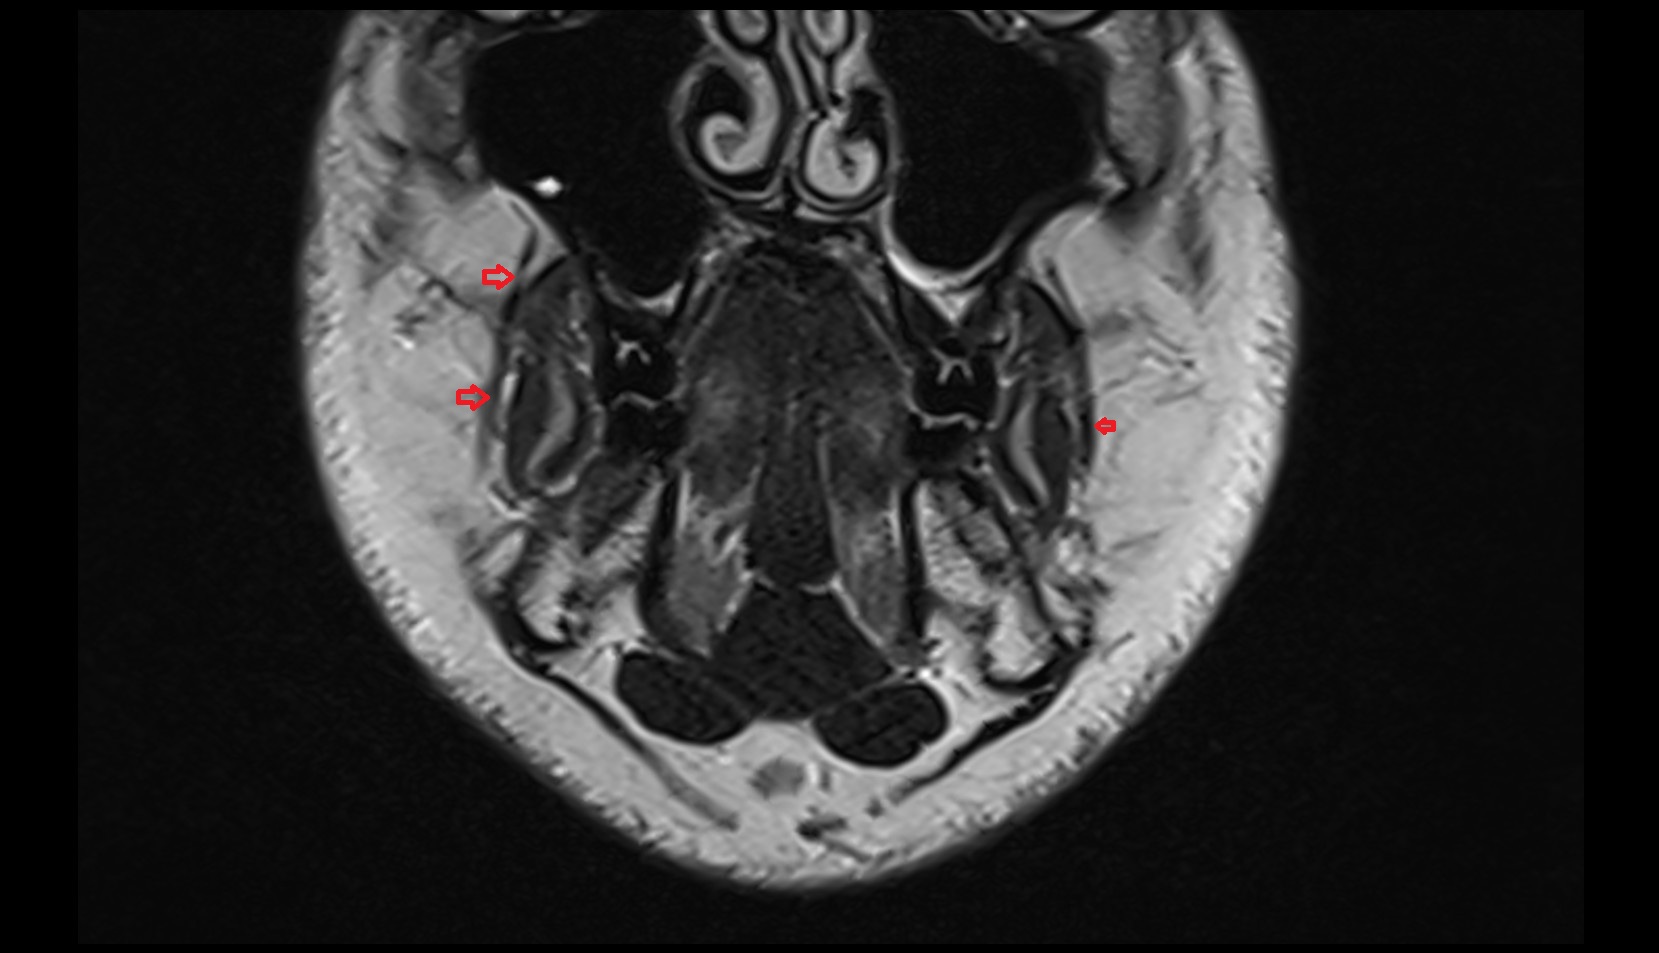

- Malar (zygomatic) lymph nodes

- Preauricular lymph nodes

- Superficial parotid lymph nodes

- Deep parotid lymph nodes

- Mastoid lymph nodes

- Occipital lymph nodes

- Superior deep cervical lymph nodes